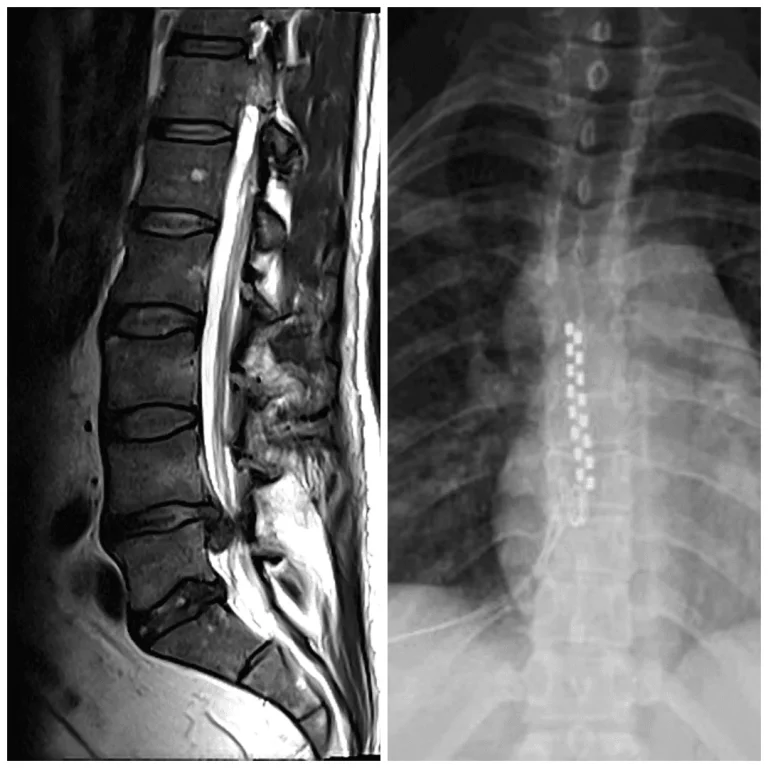

MRI and X-ray images of the spine showing hardware along the vertebral column.

Disc Injuries Left Untreated